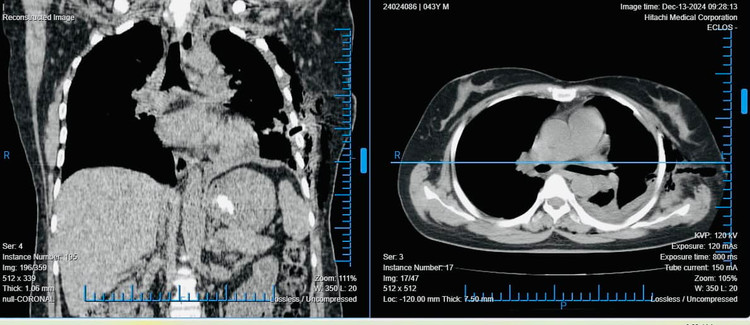

![]() |

| Hình ảnh phổi sau khi đã phẫu thuật. Ảnh TTYT huyện Tiên Yên (Phú Thọ) |

Ca phẫu thuật nội soi kéo dài hơn một giờ đồng hồ và kết thúc thành công. Sau khi lớp dày dính được giải phóng, phổi của bệnh nhân bắt đầu nở ra tốt hơn. Nhờ vào tay nghề khéo léo của các bác sĩ, bệnh nhân không bị mất máu nhiều, giảm thiểu tối đa nguy cơ biến chứng.